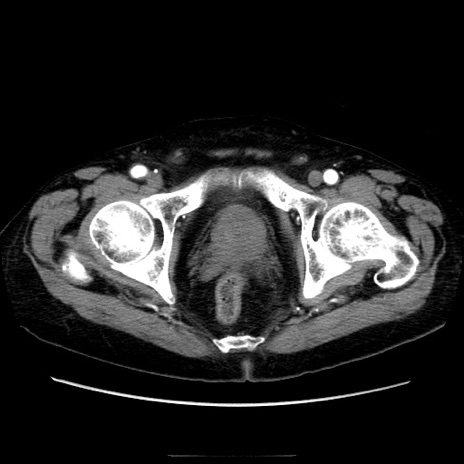

症例21(横断像)

【症例】70歳代男性

【主訴】腹痛

【現病歴】肝硬変・肝細胞癌にてかかりつけの方。約9時間前に食後より腹痛出現。症状が徐々に増悪し、嘔吐出現したため来院。

【既往歴】肝硬変、肝細胞癌(RFA、TACE後)

【身体所見】意識清明、表情苦悶様、BT 36℃、BP 129/78mmHg、P 88bpm、SpO2 97%(RA)、右上腹部から心窩部にかけて圧痛あり、反跳痛なし、筋性防御あり。

【データ】WBC 5800、CRP 0.16